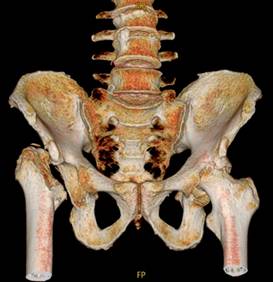

A la exploración física: postura con acortamiento de extremidad pélvica derecha, con escoliosis izquierda compensatoria. Masa ósea a la palpación correspondiendo al trocánter mayor 5 cm por arriba de la altura del contralateral. Arcos de movimiento bloqueados en la derecha, la rotación interna es limitada por dolor en cadera izquierda, el resto de exploración normal. La tomografía de cadera (Figuras 1 y 2) mostró desaparición de cabeza y cuello femoral derecho y elevación del trocánter mayor por luxación, en cadera izquierda se encontró coxartrosis severa. Se diagnosticó síndrome de Gorham-Stout, con resultados normales de laboratorio; se procedió a biopsia, la cual confirmó diagnóstico (Figura 3). Se canalizó a traumatología para colocación de prótesis bilateral.

Figura 2: Imagen tomográfica con reconstrucción en 3D, se muestran los cambios antes citados en ambas articulaciones coxofemorales.